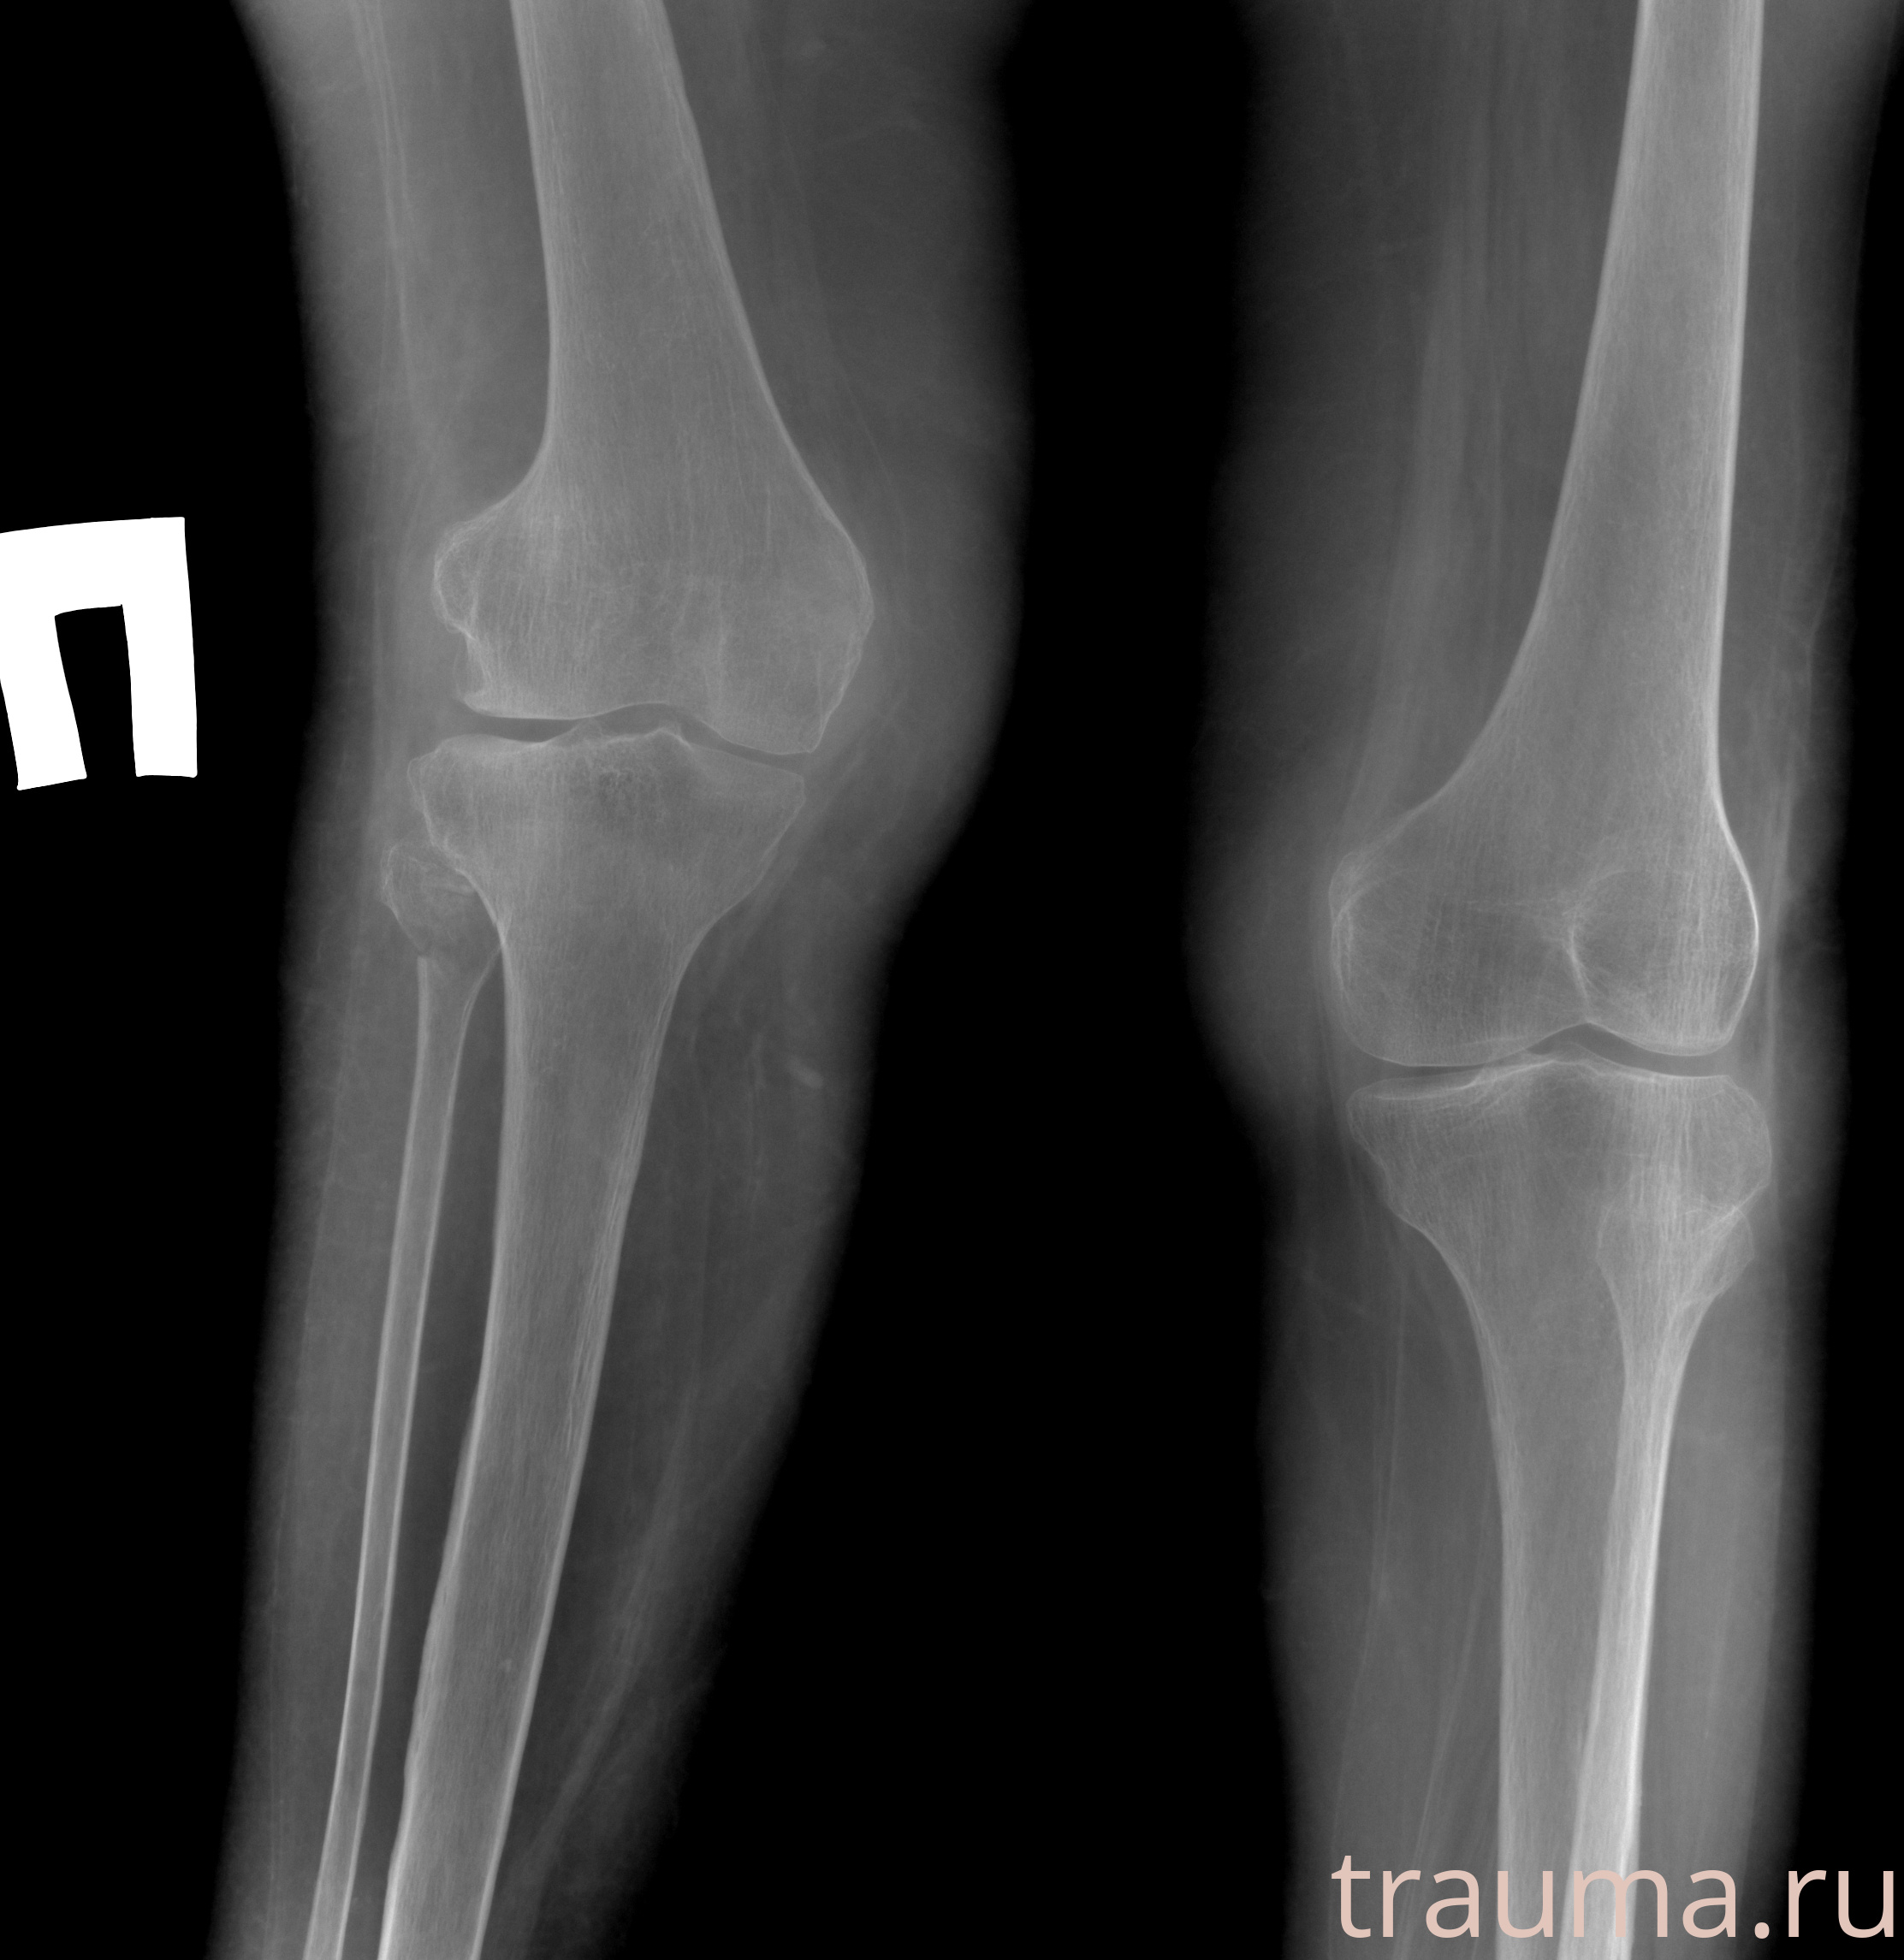

Рентгенограммы